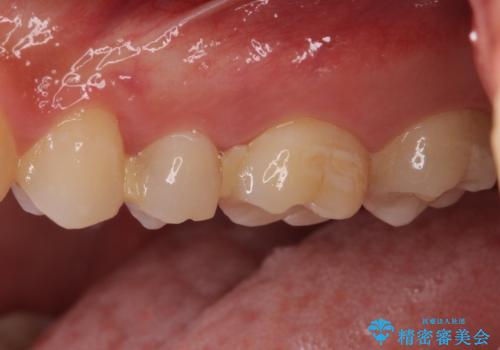

他院で治療中の歯 ゴールドインレーによる修復治療

- 近医にて虫歯治療中に転院を希望とのことで来院された患者様です。

左上奥と右下奥に治療中の歯があり、虫歯を取っている途中で仮詰めの材料が充填されている状態でした。

当初はセラミックインレーによる修復治療を希望されいましたが、カウンセリングの結果、審美性よりも安定性を優先され、PGAインレー(ゴールドインレー・白金加金合金インレー)による治療を行うこととしました。

仮詰め材を外すと虫歯が残っていたので、全てを取り除いた後に、ゴールドインレーの型どりを行いました。

ゴールドインレーをご自身で選択いただいたものの、どういった仕上がりとなるか不安を感じていたようですが、実際に装着された口腔内をご覧になり、思ったほど金属色が気にならないとのことでした。